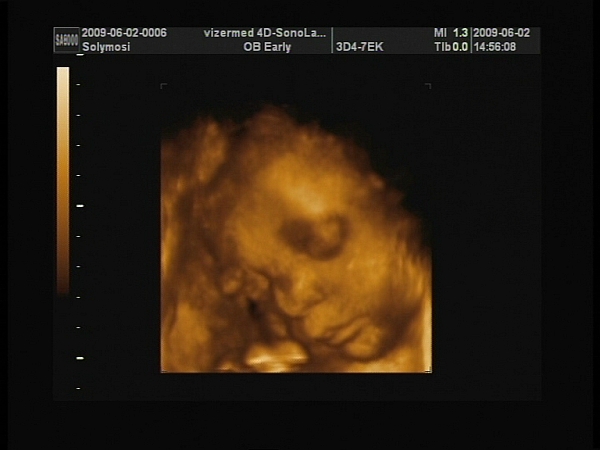

A 40 hetes átlag baba 3400g, így 38 hetesen vhol 3000g fölött járhatnak. Ez a plusz 2 hét azért nem olyan vészes, 3-4 kg között teljesen normálisnak számít a született baba, ezekkel az adatokkal meg belefér bővebben vett átlagba. Igaz, most már csak főleg hízik. Pláne, hogy két dolgot nemigen tudnak egyszerre csinálni.